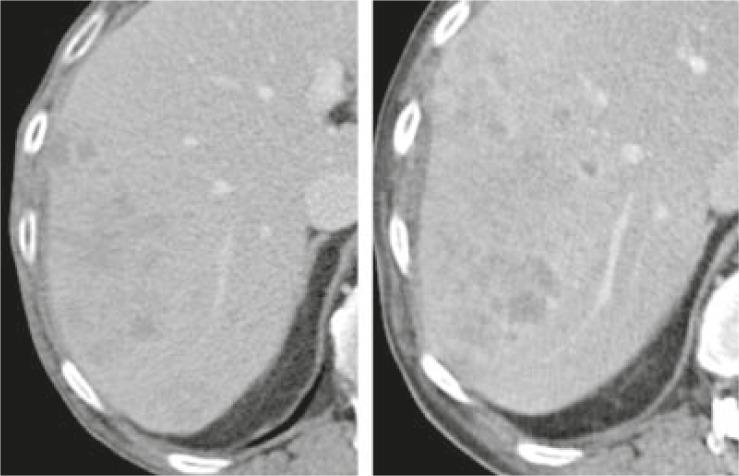

Twenty oncologic patients were included to the study with CT examinations from thorax to pelvis performed at a 64 slices CT scanner. Four readers defined and measured the size of target lesions independently at baseline and follow-up with PACS (Picture Archiving and Communication System) and LMS (Lesion Management Solutions, Median technologies, Valbonne Sophia Antipolis, France), according to the RECIST 1.1 criteria. Variability in measurements using PACS or LMS software was established with the Bland and Altman approach. The inter- and intra-observer variabilities were calculated for identical lesions and the overall response per case was determined. In addition, time required for evaluation and reporting in each case was recorded.

For single lesions, the median intra-observer variability ranged from 4.9-9.6% (mean 5.9%) and the median inter-observer variability from 4.3-11.4% (mean 7.1%), respecting different evaluation time points, image systems and observers. Nevertheless, the variability in change of Δ sum longest diameter (LD), mandatory for classification of the overall response, was 24%. The overall response evaluation assessed by a single respectively different observer was discrepant in 6.3% respectively 12% of the cases compared with the mean results of multiple observers. The mean case evaluation time was 286s vs. 228s at baseline and 267s vs. 196s at follow-up for PACS and LMS, respectively.

本研究纳入 20 名肿瘤患者,在 64 层 CT 扫描仪上进行胸部至骨盆的 CT 检查。四位读者使用 PACS(影像归档和通信系统)和 LMS(病灶管理解决方案,中位数技术,法国瓦尔布勒索菲亚安提波利斯)独立定义和测量基线和随访时的目标病变大小,根据 RECIST 1.1 标准。使用 Bland 和 Altman 方法确定 PACS 或 LMS 软件测量中的变异性。计算相同病变的观察者内和观察者间变异性,并确定每个病例的总体反应。此外,还记录了每个病例评估和报告所需的时间。

对于单个病变,观察者内变异性中位数范围为 4.9-9.6%(平均 5.9%),观察者间变异性中位数范围为 4.3-11.4%(平均 7.1%),考虑到不同的评估时间点、影像系统和观察者。然而,对于分类总体反应必需的Δ总和最长直径(LD)的变化的变异性为 24%。与多位观察者的平均结果相比,单个观察者或不同观察者评估的总体反应评估结果不一致的病例分别占 6.3%和 12%。使用 PACS 和 LMS 的平均病例评估时间分别为 286s 与 228s(基线)和 267s 与 196s(随访)。